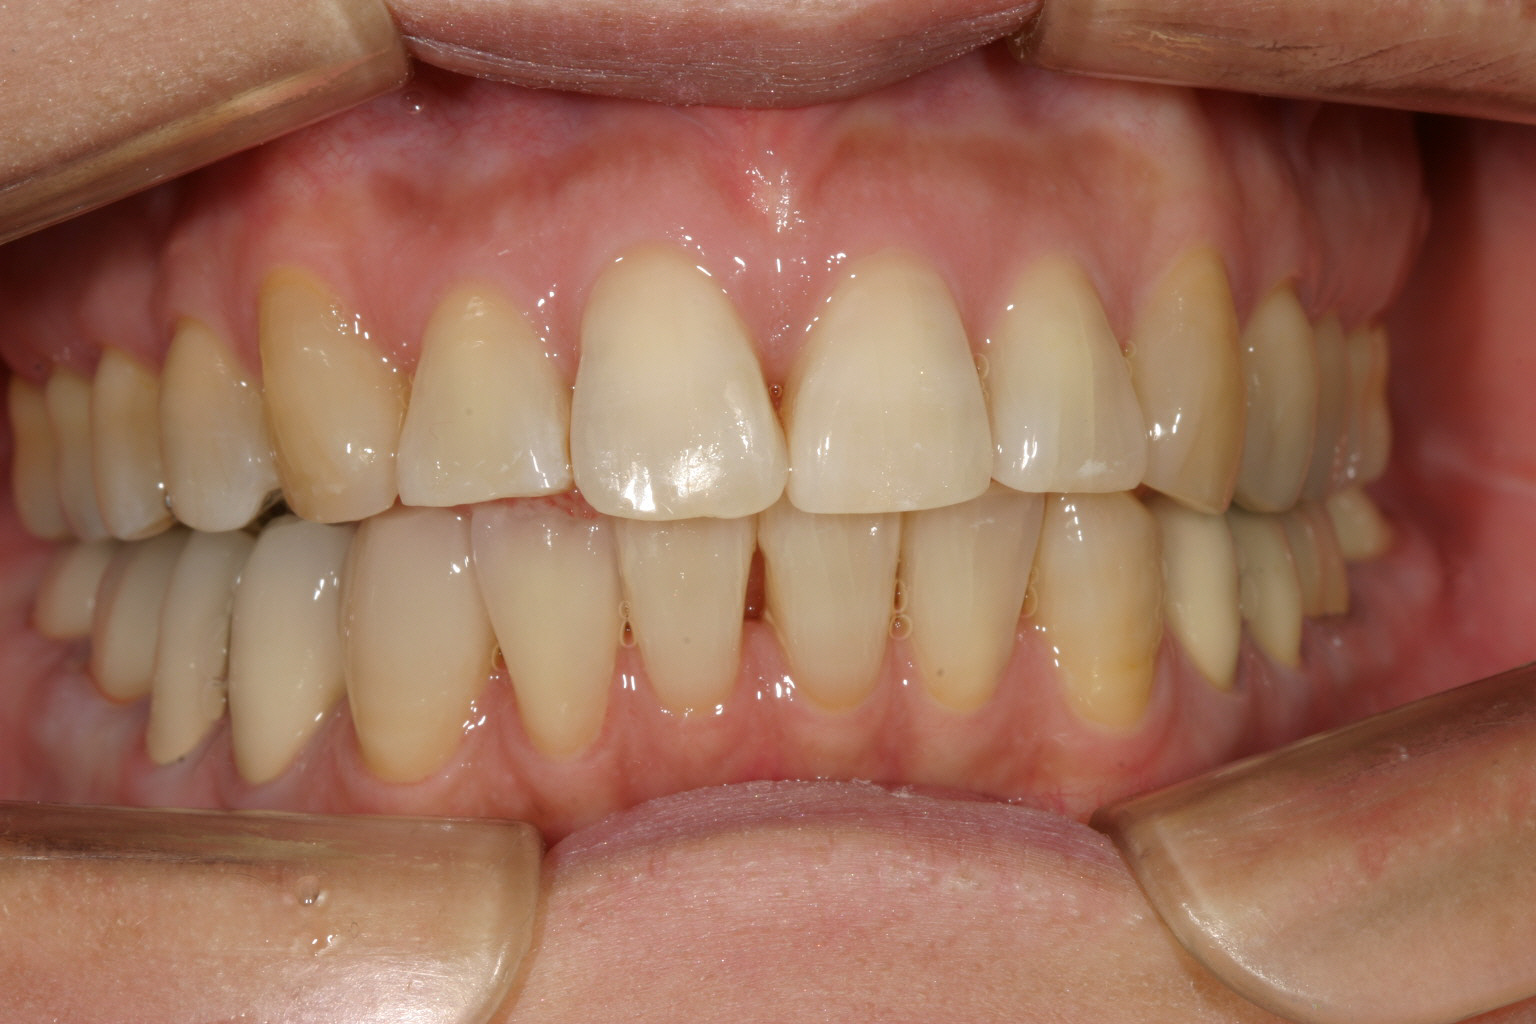

側面観はオーバージェットも改善してます。

綺麗に並びました。

綺麗に咬合してます。 最初の正面観見て頂ければ正中が左にシフトし改善しているのが分かります。